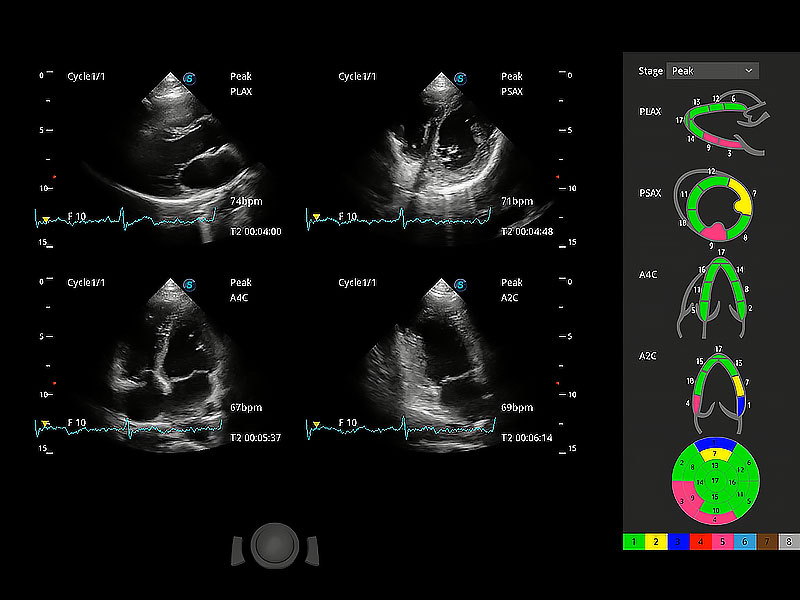

• MQA 心肌定量分析

通過心肌識別技術(shù)與二維斑點追蹤技術(shù)相結(jié)合,對心臟的超聲圖像進(jìn)行量化分析。計算心肌17個節(jié)段的應(yīng)變、應(yīng)變率、速度、位移等,并通過牛眼圖的形式進(jìn)行呈現(xiàn)。

• Stress Echo 負(fù)荷超聲心動圖

具備多種協(xié)議可選,同時支持17階段劃分法和專業(yè)的SE報告。

(犬)四腔心MQA